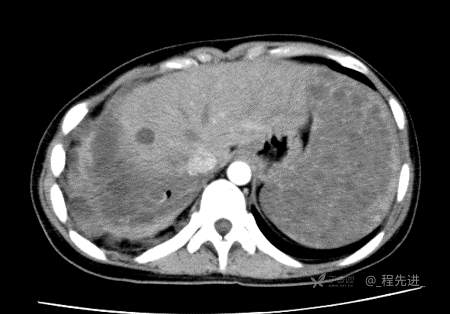

患者性别:女

患者年龄:26岁

简要病史:反复胸闷、气喘、咳嗽半年